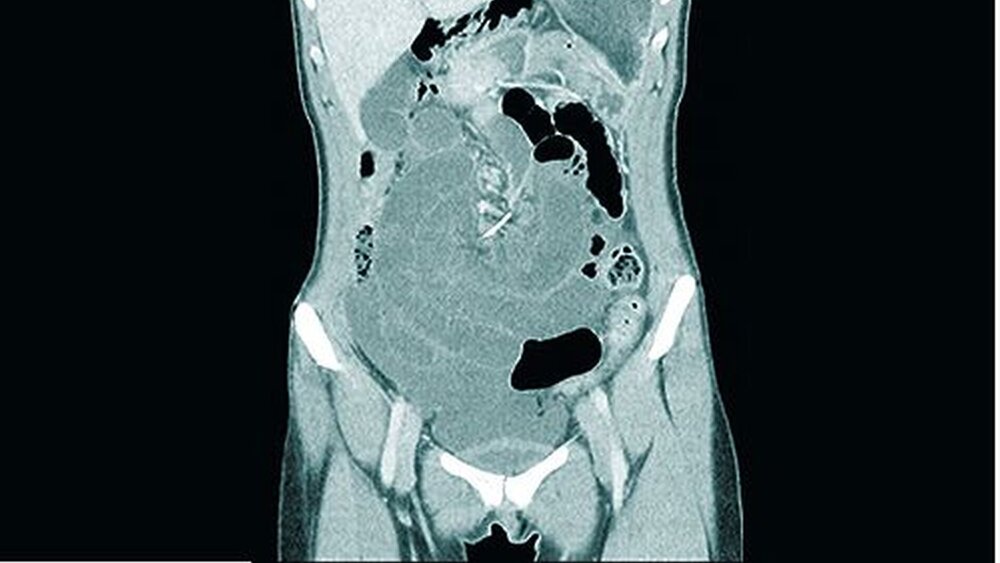

Bei der zweiten Untersuchung stellten die Ärzte dann fest, dass sich das Bauchfell entzündet hatte. Das CT zeigte einen dünnen Metalldraht an der Mesenterialwurzel, also an der Stelle des Dünndarms, an der das Bindegewebe mit der Bauchwand verwachsen ist (Abbildung 1).